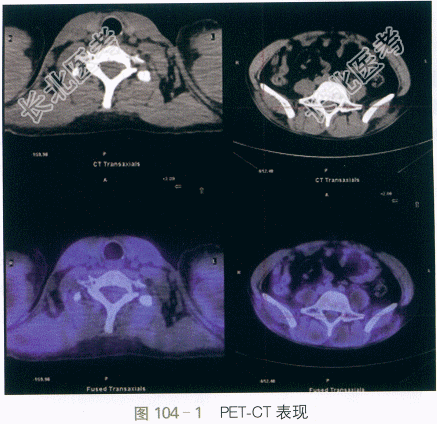

血常规、尿常规、凝血功能(-);24h尿蛋白定量0.42g;肝肾功能:A/G38/25(g/L),ALT/AST 147/410(IU/L),ALP/GGT73/35(IU/L),Scr76μmol/L;CK16461IU/L,CK-MB367IU/L,CK-MM16094IU/L;TC/TG5.29/1.97(mmol/L);ESR35mm/h,hsCRP8.3mg/L,RF<7IU/ml;SCC4.8ng/ml,NSE28.0ng/ml,CA15-325.4IU/ml。动脉血气分析:pH7.44,PO275mmHg,PCO234mmHg,SBE2.8。自身抗体:ANA颗粒1:1000(+),抗ds-DNA抗体10.0IU/ml,抗核小体抗体2.0RU/ml,抗JO-1抗体(+),余抗ENA谱(-),自身免疫性肝炎相关抗体均(-),ANCA(-)。肺部HRCT:双下肺间质性炎症伴少许间质纤维化。心超:左房增大,肺动脉压力30mmHg,LVEF70%。骶髂关节MRI:双侧髂腰肌、腹直肌、竖脊肌及臀部肌群弥漫性异常信号,考虑肌炎表现(见图104-2)。肌电图:四肢肌肉肌源性损害。